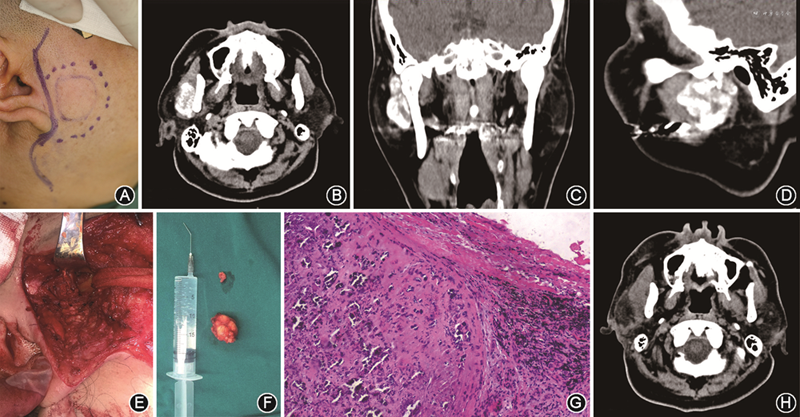

(1)临床检查:右侧耳屏前髁突外侧相当于耳垂处有一大小2.0 cm×3.0 cm的肿块(图4A),扪诊质地中等偏硬,活动度差。双侧颞下颌关节区有张口弹响,开口度、开口型正常。无面神经受损症状。

(2)影像学检查:螺旋CT示右颞下颌关节外侧,右侧咬肌中后部至腮腺见不规则团状软组织块影,界限不清,边缘不规整,其内见大小不等斑片状絮状高密度影及钙化影,边缘毛躁。右下颌支和右颞下颌关节髁突未见明显异常骨质吸收或增生现象,骨皮质边缘光滑连续(图4B~D)。

(4)诊断及治疗计划:右颞下颌关节区病变待查,考虑TC或滑膜软骨瘤病。拟行右侧颞下颌关节区病变切除术。

(5)治疗过程:术中做耳前S形切口,将咬肌和腮腺一并向上翻起,在其深面暴露出肿物,包膜完整,质地中等偏硬,有一蒂与髁突关节囊相连。将肿物、蒂部和部分关节囊一并切除(图4E)。充分止血冲洗后关闭术创(图4F)。病理诊断为:右颞下颌关节区TC(图4G)。患者术后1周出院时术创皮肤对位良好,无明显红肿及渗出,咬合关系正常,轻度张口受限,右眼轻度闭合不全,右额纹变浅,右侧嘴角稍向左偏斜。

(6)术后随访:术后随访3个月,患者恢复良好,开口度和开口型正常,咬合关系良好。右眼轻度闭眼不全,其余面神经损伤症状已消失。术后6个月闭眼功能恢复。术后CT检查示:右侧颞下颌关节区不规则团块状软组织肿块已去除,术区呈腔状低密度改变,边界稍显模糊。